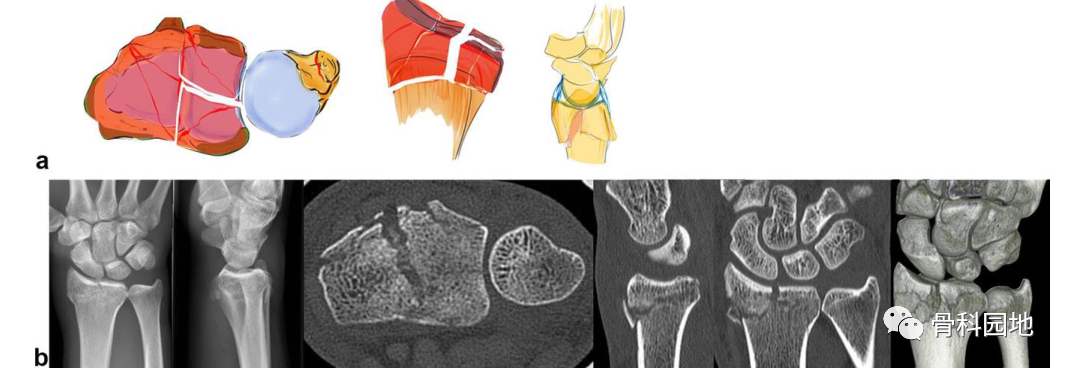

注:在部分关节内骨折中,可以观察到六种不同的模式。至少有一个角保持完好(a) 显示了外在韧带的起源,这似乎加强了骨骼 (b)

注:径向作用力沿头状骨、舟状骨和月骨指向茎突,茎突沿韧带止点断裂并沿桡侧掌侧或背侧方向脱位(见图a)。茎突和月骨形成一个由韧带连接的单元。在外伤的情况下,头状骨突出在月骨和舟骨之间,导致舟月韧带断裂。由于韧带附着,腕骨倾向于径向半脱位(见图 b)。

2、掌侧关节骨块

注:可以是大的或较小的边缘碎片。可能发生掌侧脱位,而背侧韧带保持完整 (a)。掌侧骨块:重要的尺桡韧带和尺腕韧带的起源 (b)。向掌侧脱位(c)。掌侧骨折从尺侧延伸到桡侧(d)。在 X 光平片上很容易忽略小的掌侧尺骨骨块,但轴位 CT 扫描容易显示该骨块 (e)